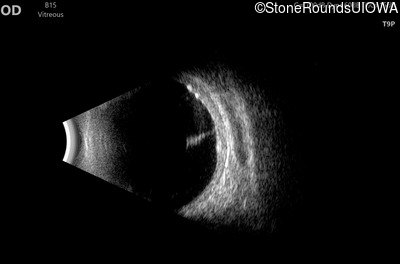

B-Scan Ultrasonography - Right - 20/200 sc

Exemplar